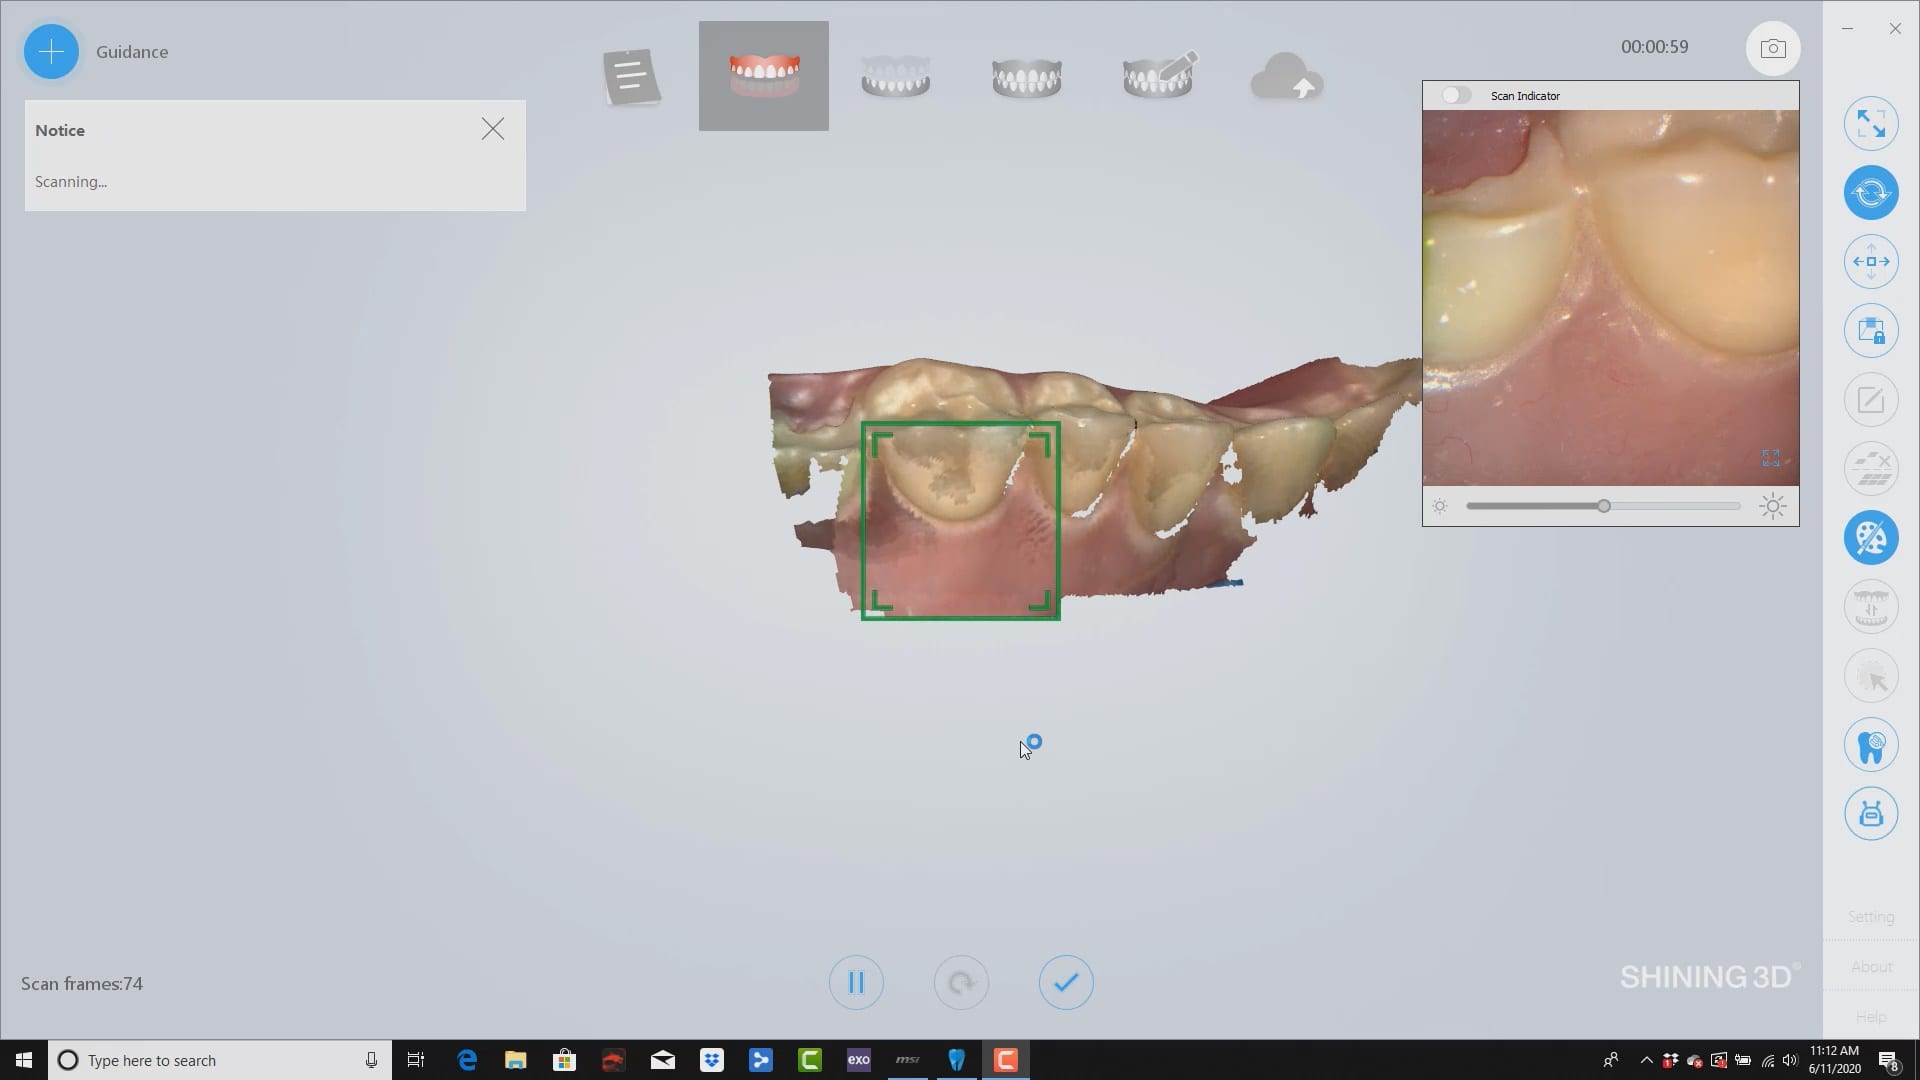

Virtual Extractions for Overdenture with Shining 3D

June 11, 2020upper denture duplicated with shining 3d. only needed the occlusal and buccal surfaces as the case is for a lower overdenture over immediate extractions, on healed implants. went ahead and […]